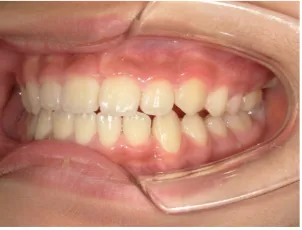

治療中③小2(7y8m):JUMP 受け口が改善

治療中④小2(8y2m)~小3(9y1m):QHとBHで拡大・アーチ形態の修正、ブラケットで前歯の並べ替えまで終了

治療中⑥小4(10y2m):モノブロック装置継続中 上下正中改善中

治療中⑦小5(11y3m):モノブロック装置継続中

| 行ったご提案・診断内容 | 成長期に行う治療と咬合治療をご提案 受け口用ファンクショナルアプライアンス(写真②③)からスタートし、小2以降で上下顎の拡大・歯列弓の形態修正・前歯の並べ直し(写真④)を行いその後、モノブロック(筋機能的咬合誘導)装置(写真⑤)へ移行し、受け口の再発予防と永久歯を適切な咬み合わせに誘導し、必要によりマルチブラケット法へ移行する治療方法を提案しました。 成長期治療(成長時期にお口の環境を整える治療) 2年生以降から 咬合治療 |